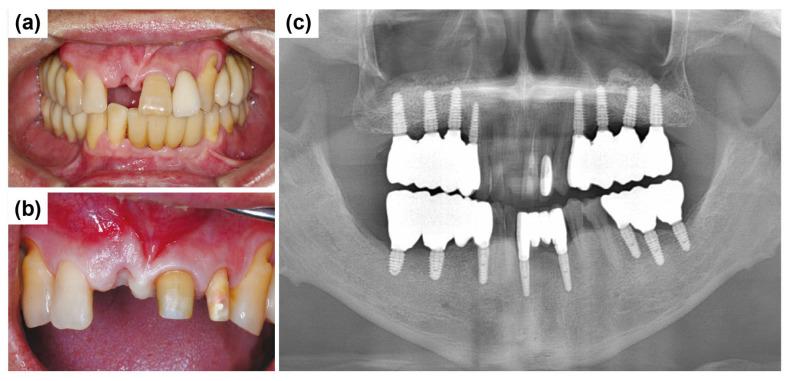

: The rehabilitation of severely resorbed anterior alveolar ridges presents significant clinical challenges due to esthetic demands and the limited bone volume in this region. Basal cortical implants, which are designed to engage dense basal bone, could offer an alternative by providing stable anchorage in compromised sites. : This report evaluates the ARi Implant System, which features cortical anchorage and a calcium-incorporated nanostructured surface (XPEED) in two anterior ridge defect cases. Soft tissue augmentation using a vascularized interpositional periosteal (VIP) flap was applied in one case, and biphasic calcium phosphate (BCP) grafting and collagen membranes were employed for ridge contouring in both cases. : At a two-year follow-up, both cases showed stable peri-implant tissues and satisfactory esthetic results. : Although basal cortical implants provide good primary stability, their use does not eliminate the need for bone augmentation, especially in the anterior esthetic region. Future clinical studies are required to substantiate long-term outcomes and broader applicability.

摘要

严重吸收的前牙牙槽嵴的修复由于美学需求和该区域有限的骨量而面临重大临床挑战。基底皮质种植体旨在与致密的基底骨结合,通过在受损部位提供稳定的锚固,可提供一种替代方案。:本报告评估了ARi种植系统,该系统在两个前牙嵴缺损病例中具有皮质锚固和含钙纳米结构表面(XPEED)。其中一例采用带血管蒂的间置骨膜(VIP)瓣进行软组织增量,两例均采用双相磷酸钙(BCP)移植和胶原膜进行嵴轮廓塑形。:在两年的随访中,两例均显示种植体周围组织稳定,美学效果满意。:尽管基底皮质种植体提供了良好的初期稳定性,但使用它们并不能消除骨增量的需求,尤其是在前牙美学区域。需要未来的临床研究来证实长期效果和更广泛的适用性。